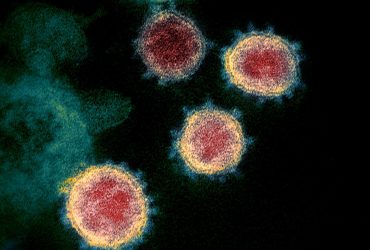

Uma nova modalidade de teste rápido para detecção de possíveis lesões ...